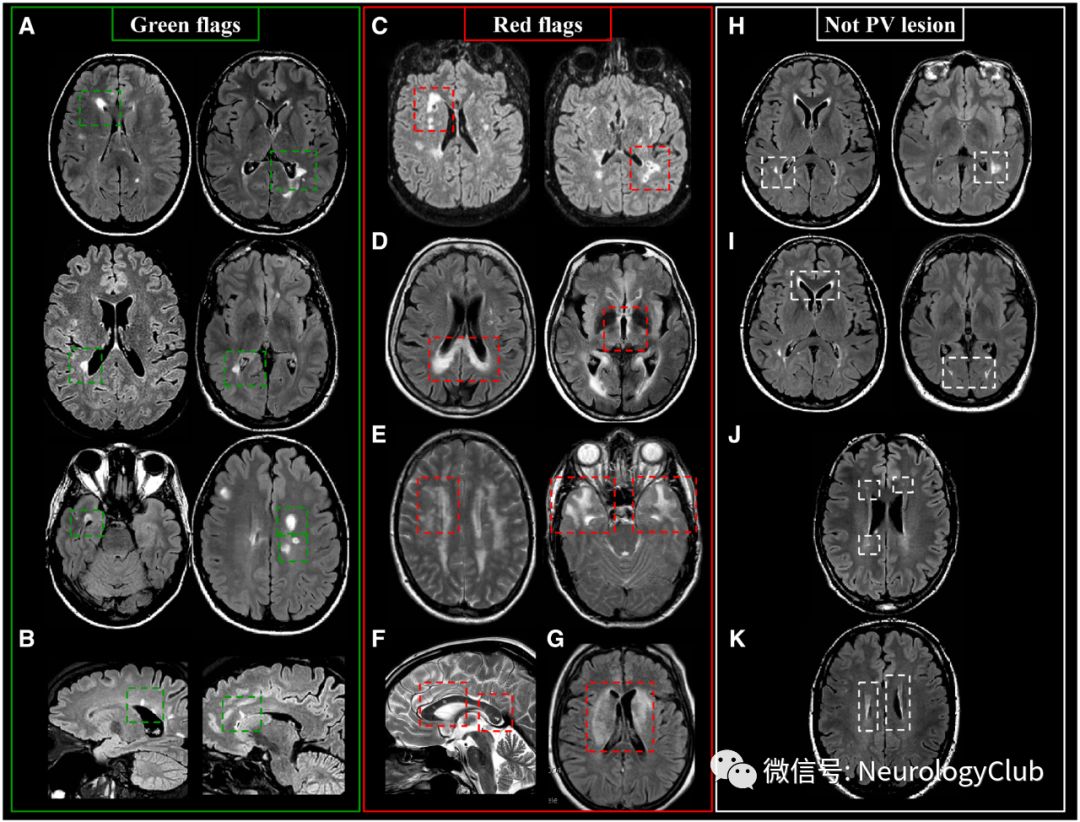

MS病灶通常分布在两个半球,早期多为轻度不对称性。病灶可见于中枢神经系统任何部位,相对于其他引发白质病变的疾病而言,MS常累及特定的白质区域,如脑室周围、皮质下白质、胼胝体、幕下(尤其是脑桥和小脑)和脊髓(尤其是颈段)。MS典型病灶(绿旗征)与非典型病灶(红旗征)见表2,相关影像学描述见图1-5。

图1:MS患者脑室周围典型和非典型病灶以及不应该计数在内的病灶;左:绿旗征:(A)提示MS的脑室周围病灶;(B)垂直于胼胝体的脑室周围病灶(Dawson手指征);中间:红旗征:(C)累及脑室旁及深部灰质的多发白质病灶,提示缺血性小血管病灶;(D)NMOSD患者广泛的胼胝体压部受累和双侧间脑病灶;(E)常染色体显性遗传性脑动脉病伴皮质下梗死(CADASIL)累及深部白质、外囊和颞叶的多发病灶;(F)胼胝体内“雪球样”病灶(Susac综合征);(G)系统性红斑狼疮累及双侧白质和深部灰质的弥漫性和广泛性病灶;右:不应认为是脑室周围病灶:(H)不接触脑室的病灶:(I)脑室前后角对称病灶(侧脑室带帽征);(J)病灶长轴小于3mm;(K)邻近侧脑室的对称线性高信号;PV=脑室周围